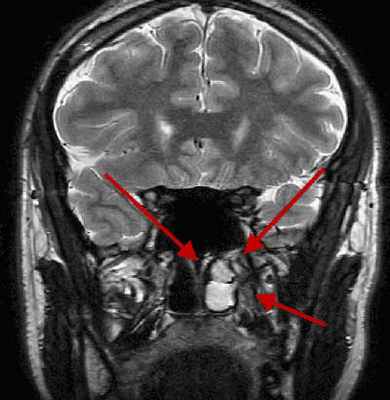

Признаки микроаденомы на МРТ снимках

Косвенными признаками микроаденомы на МРТ снимках служат:

- скошенность дна гипофиза;

- приподнятость диафрагмы седла;

- отклонение ножки;

Прямые признаки микроаденомы:

- увеличение анатомических размеров гипофиза;

- отсутствие накопления или запоздалое накопление контрастного вещества

Расшифровка результатов

Гипофиз – это небольшая железа, локализованная в ямке турецкого седла клиновидной кости. Ее размеры при отсутствии патологических процессов не превышают 1,5-2 см. От полости черепа гипофиз отделен диафрагмой седла, а участок задней доли железы соединяется с гипоталамусом. Как правило, о наличии аденомы гипофиза сигнализируют следующие патологические изменения:

- Деформация дна гипофизарной ямки;

- Выраженная асимметрия железы;

- Неоднородная структура гипофиза очагового характера;

- Смещение воронки от срединной линии.